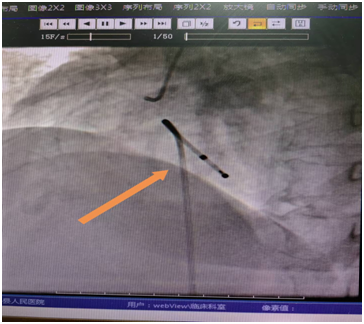

结合患者病史,考虑为急性下壁心梗,右冠闭塞,房室结缺血所致,患者心率显著减慢,有发生猝死可能,需立即开通右冠,恢复房室结血运,方能恢复心率。患者病情危重,经心内科介入团队讨论后,决定行临时起搏器治疗保驾下急诊冠脉造影+支架植入术。与患者家属充分沟通后,家属同意手术。随即转往手术室,在DSA指导下,首先完成临时起搏器植入治疗。如图:

植入临时起搏器后,患者心率维持在起搏心率60次/分,为急诊支架植入术提供强有力的保障,避免术中猝死。急诊冠脉造影提示右冠状动脉急性闭塞,造影图示: